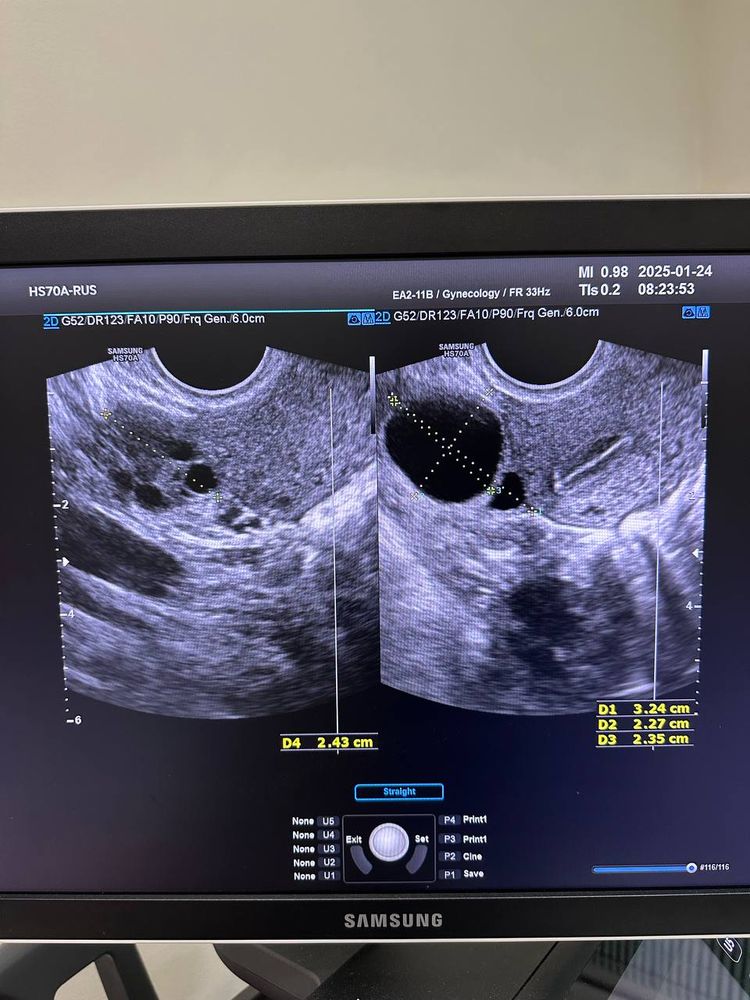

Первый раз была на узи на 7 ДЦ эндометрий 1мм, на 12 ДЦ была овуляция. На 15 ДЦ эндометрий 7,8 и нашли непонятное тело 23мм. Узист считает, что это киста, врач гинеколог считает, что это фолликул, который скоро превратится в желтое тело. Вопрос в следующем. Врач назначила принимать дюфастон с 16ДЦ 1т х2р 10 дней. Если тест будет отрицательный, то отменять, если положительный то продолжать пить. Так же свечи индомецетиловые(точно не могу прочитать из рецепта) на случай если это действительно киста. Повторной узи не назначили. Прислушаться к этим советам? как считаете? Фото прилагаю

Лизик , эндометрий трехслойный у вас на момент проведения узи, это соответствует первой фазе цикла, т.е. до того момента, как образовалось желтое тело. Если бы это у вас была киста желтого тела, то эндометрий бы уже трансформировался, он же под действием прогестерона меняет свою структуру. Я бы не сказала, что критично тонкий, соответствует минимальной границе (от 7)